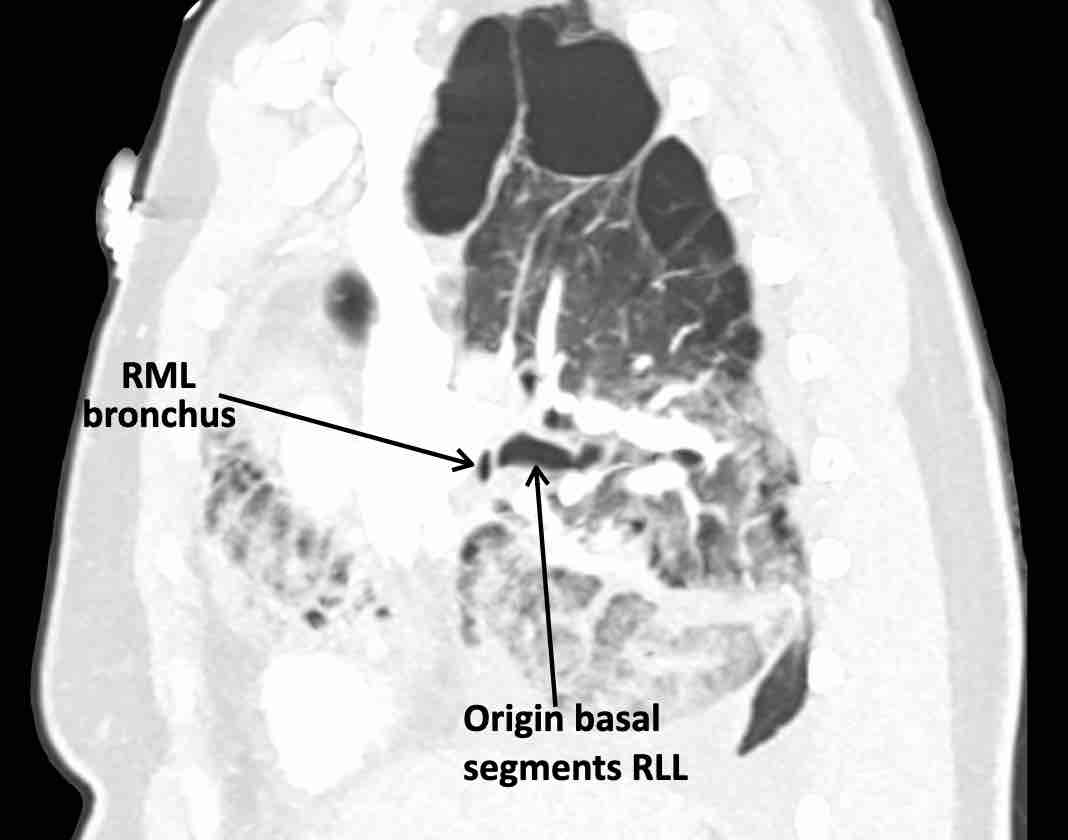

Các hình ảnh này của một bệnh nhân nữ 65 tuổi sau khi đã cắt thùy trên phổi phải trước đó.

Theo dõi lần lượt các phế quản giúp xác định mỏm cắt thùy trên phổi phải (RUL), phế quản thùy giữa bị tắc nghẽn và các phế quản thùy dưới còn thông.

Điều này xác định mô phổi bị di lệch xuống dưới chính là thùy giữa phổi phải (RML), thấy rõ nhất trên mặt phẳng đứng dọc.

Thùy giữa phổi phải bị phù nề và không còn được tưới máu.

Ngoài ra còn thấy hình ảnh ứ máu và xẹp phổi ở các phân thùy đáy của thùy dưới phổi phải (RLL), hiện nằm phía trên thùy giữa phổi phải đã bị nhồi máu.